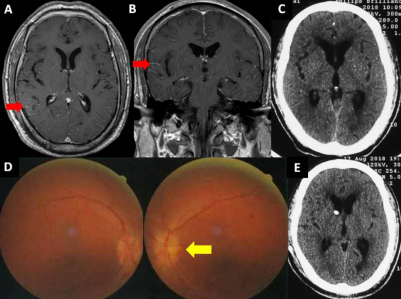

病例:肺癌脑膜转移,脑积水,颅内压增高

男,52岁,发现肺癌9个月,内科治疗,视物不清10天,头疼1周。患者视力下降明显且进展较快,腰椎穿刺压力大于330mmH2O,眼底检查可见视乳头水肿,视力:右眼:眼前手动,左眼:1m手动。患者为肿瘤细胞脑膜转移,阻塞蛛网膜颗粒,引起脑脊液循环障碍,造成颅内压增高,手术选择脑室腹腔分流术,术后颅内降低,头痛消失,视力好转,右眼:眼前手动,左眼:30cm数指。

图:A 轴位强化MRI,B冠位强化MRI,可见脑沟内线样强化(红色箭头所示),为肿瘤的脑膜播散转移; C 术前CT可见脑室轻度增大,D 术前眼底照相,视乳头水肿(黄色箭头),E 术后CT可见分流管脑室端放置位置良好。